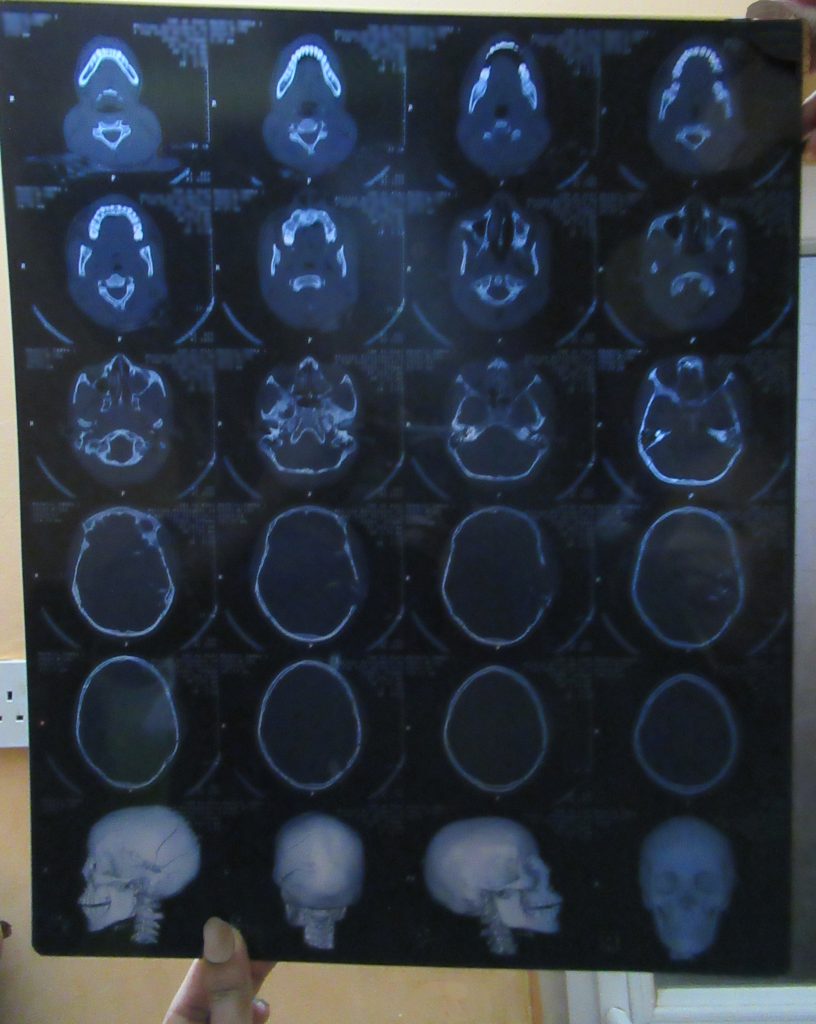

physical examination, which found that Nassir has

difficulties in motor function and speech while retaining

the ability to think and draw, are entirely consistent with a

deep left-sided injury to the parietal lobe of the brain.

PHR’s clinician said that his continued seizures and his

inability to articulate clearly three months after the injury

raise concerns about Nassir’s ability to recover fully

Fifteen-year-old Nassir[21] often attended the protests when he was not working. On the morning of June 3, he was at the sit-in, where he sustained a gunshot wound behind the left ear. Nassir was admitted to Dar el-Elaj Hospital at 6 a.m. on June 3; the medical staff did not expect him to survive. Although it was difficult because of the ongoing violence, the staff located a neurosurgeon to remove the bullet from his brain.

According to a clinical consultation carried out by PHR’s investigator, Nassir’s continued seizures and inability to articulate clearly more than three months after the injury raise concerns about his ability to recover fully. For many like Nassir, the extreme violence unleashed upon them on June 3 is highly likely to lead to a lifetime of chronic pain and disability.